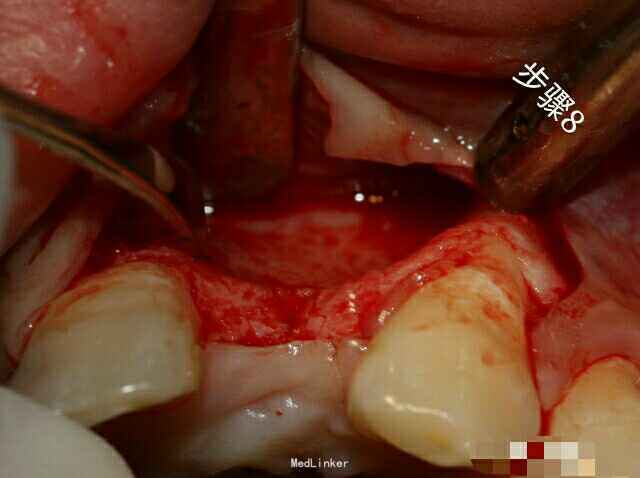

局部浸润麻醉 切口设计为在23远中加垂直切口,缺损区牙槽嵴切口。21龈沟切口 全厚层瓣翻开粘骨膜。 使用刮匙和骨刨彻底清理骨面软组织 环形骨钻 使用环形骨钻在缺损牙槽骨根方取自体骨,同时创造血供区 环形骨钻直接获取自体骨粉末 使用小号麻花钻在骨面上预备更多营养孔 骨面血供良好 选择缺损区大小相仿的钛网(已消毒) 使用金冠剪修正钛网外形,利于塑性和就位 用自体骨和骨粉混合 缺损区植骨 少量植骨后,钛网就位并检查就位状况 选择合适膜钉 用膜钉固定钛网 继续植骨,确保受植区骨量充足 植骨后骨量明显充足 软组织减张后骨粉和钛网上部覆盖可吸收性胶原膜 关闭创口,严密缝合 术后加压冰敷,医嘱。 完成后CBCT检查,术后骨宽度良好,约半年后复诊。随诊。